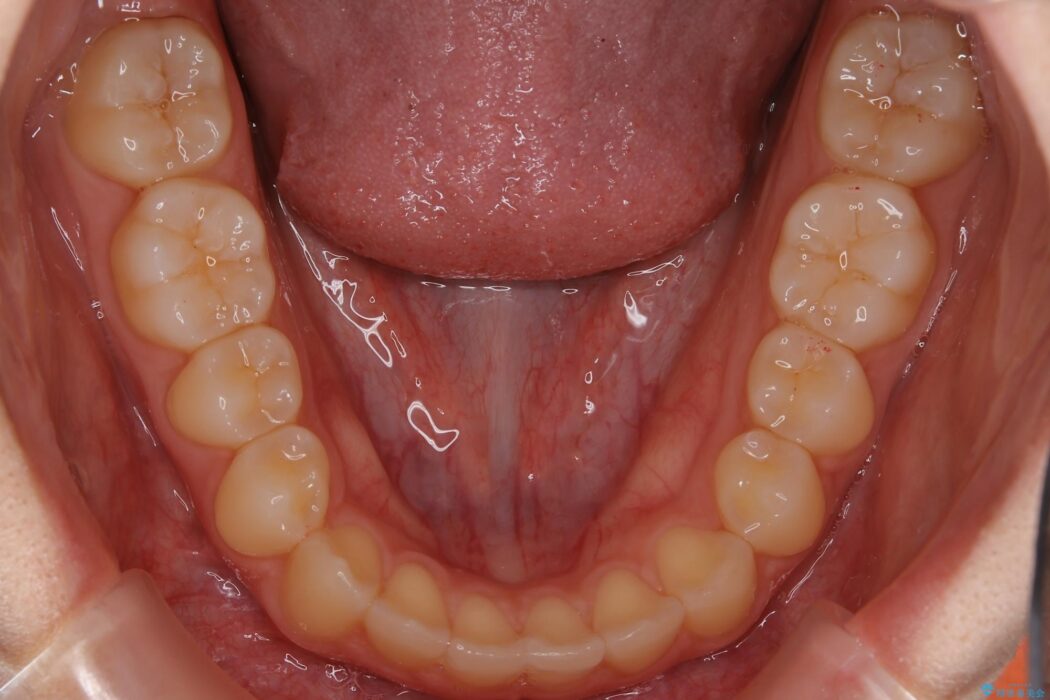

すきっ歯を改善したいとご来院された患者様です。

マウスピース14枚・期間4ヶ月で主訴であるすきっ歯を改善し、治療を終えることが出来ました。